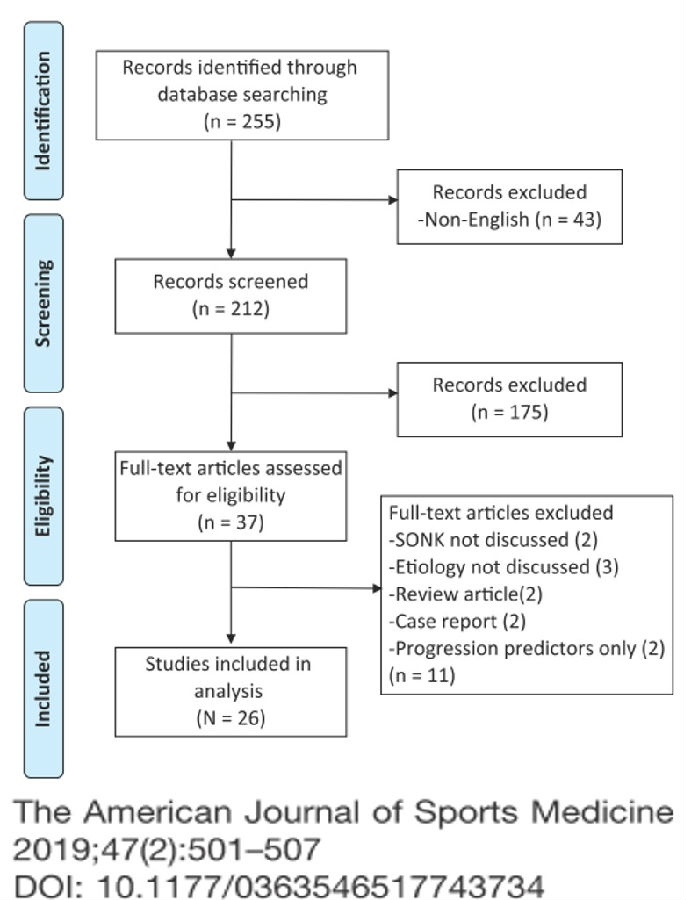

SONK的真正病因尚不清楚,目前主要3种学说:①创伤源性理论,股骨髁在机械应力作用下发生软骨下区微骨折;②血管源性理论,股骨髁血供中断导致局部血液循环障碍;③应力源性理论,半月板损伤、突出和膝内翻。

③应力源性理论:

关于SONK与内侧半月板损伤,在一项研究中,关节造影检查27个SONK膝关节中发现有21个(78%)半月板撕裂,半月板碎片边缘的应力集中可能导致股骨髁缺血性坏死。

表明老年患者通过关节造影早期发现内侧半月板撕裂并及时治疗,对于避免“自发性”骨坏死的晚期变化可能很重要。

另一项研究纳入26篇文章,其中有21篇(80.7%)涉及半月板在SONK发展中的作用,启示SONK与半月板撕裂或半月板切除术后的发展有关,而内侧半月板撕裂、后根撕裂更常见。

SONK与内侧半月板后根部损伤,有国外学者在SONK患者中通过MRI及关节镜检查,常可发现合并内侧半月板后根部的撕裂,该发生率可达到80%(24/30), 15例完全撕裂,9例部分撕裂。结果表明SONK可能与内侧半月板后根部撕裂后,导致股骨负重区的应力集中、软骨下骨髓水肿有关。